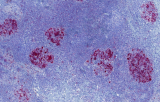

- Pannelli orientati alle entità per neoplasie linfoidi:

- Linfoma follicolare: tipici pattern di co-espressione (es. CD10 con BCL2 aberrante).